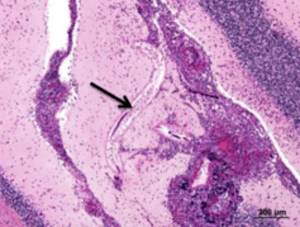

If a dog eats an infectious snail or slug, larvae leave the intestinal tract and make their way to the spinal cord at the tail-end of the dog, then migrate through the tissues of the nervous system, heading towards the brain. (The same thing happens in human patients.)

The clinical manifestations of neural angiostrongyliasis (the name of the disease in people caused by rat lungworm migrating through the spinal cord and brain) are just as devastating and tragic in human patients, especially if a baby or infant is infected.